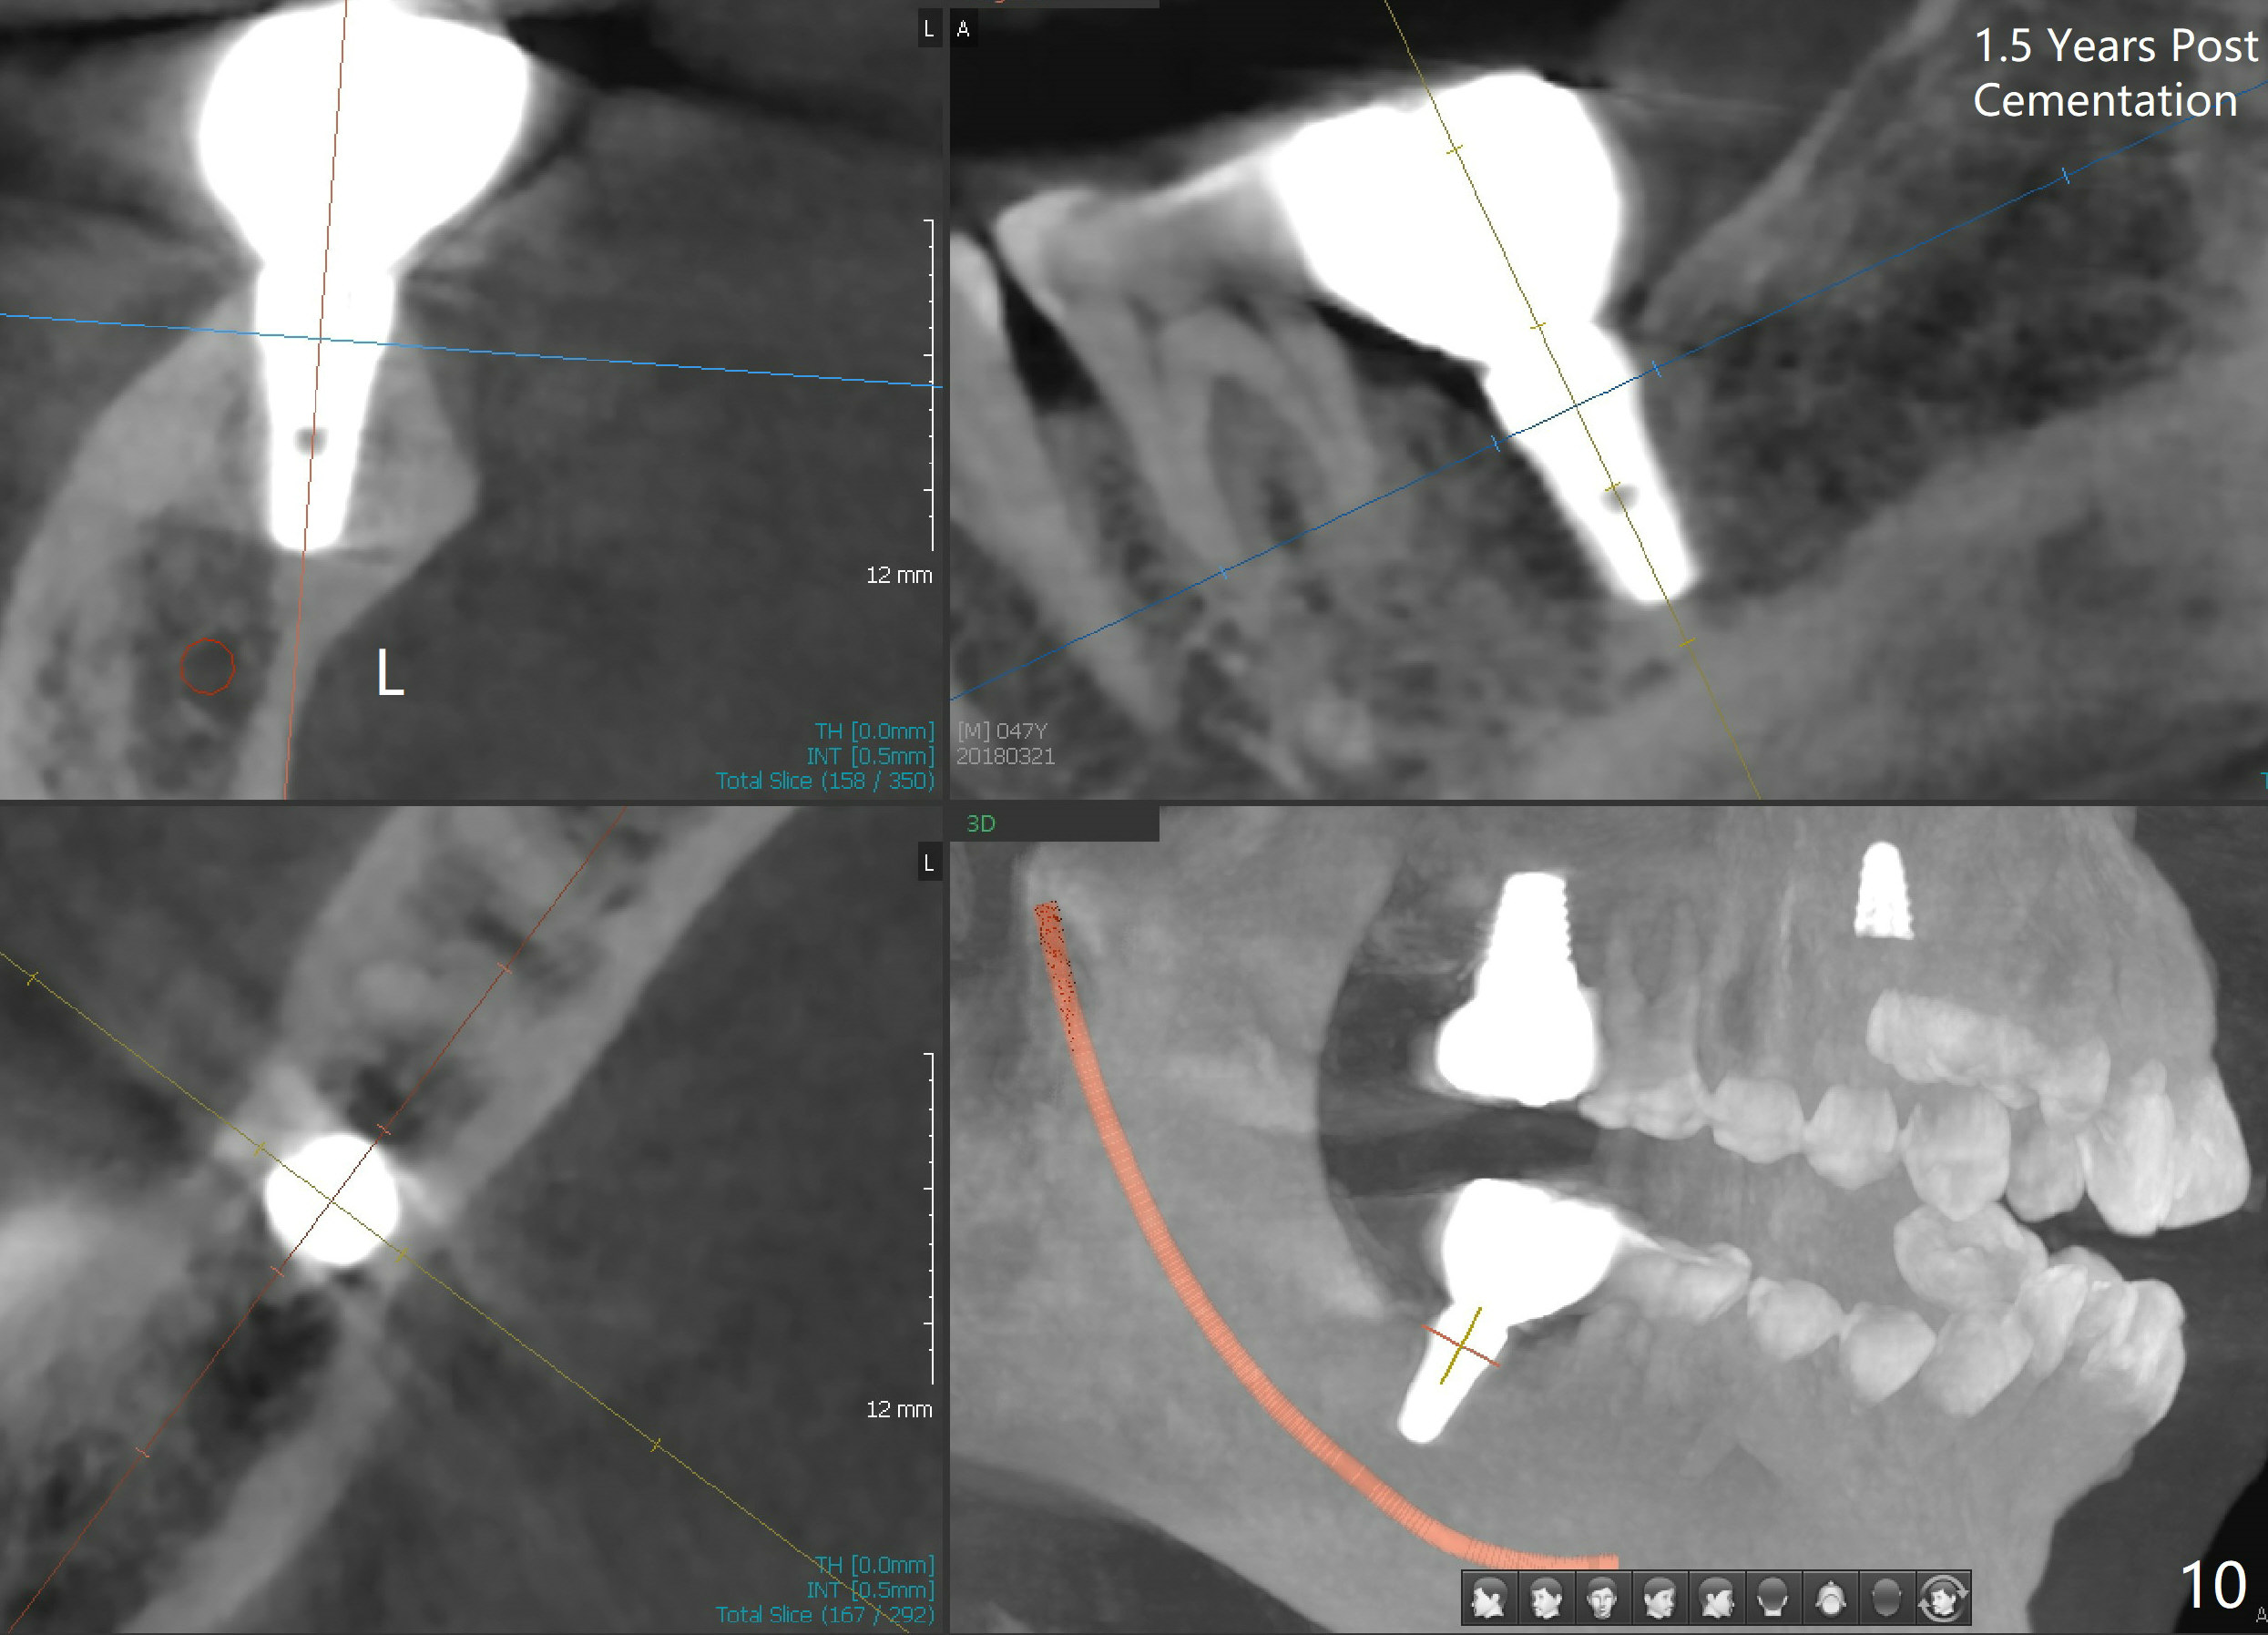

There appears to be bone loss coronally 15 months postop (Fig.8). There is no bone loss 1 year post cementation (2 years 3 months postop, Fig.9). If the implant were longer, it might perforate the lingual (L) plate (Fig.10 (1.5 years post cementation)).